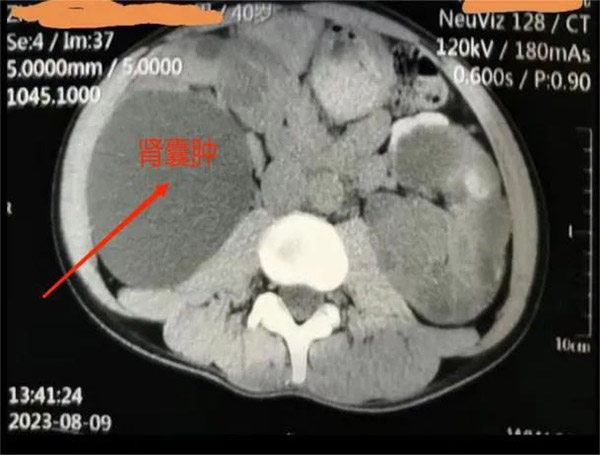

▲患者肾囊肿影像

38岁的王先生是一名多囊肾病合并巨大囊肿患者,因为工作原因需要经常出国。近半年来,他的囊肿逐渐增大并出现腰痛、腹胀的压迫症状,严重影响了王先生正常工作和生活。

肾内科主任洪敏接诊后,对王先生进行了详细的检查,结合其病情和身体情况,决定实施超声引导下经皮穿刺抽液囊肿硬化治疗。

“超声引导下经皮穿刺抽液硬化治疗能清晰显示囊肿的位置、大小、深度以及和周围脏器的关系,实时观察穿刺治疗过程,操作简便、安全,无辐射,更适合不愿接受外科手术的王先生。”洪敏主任表示。